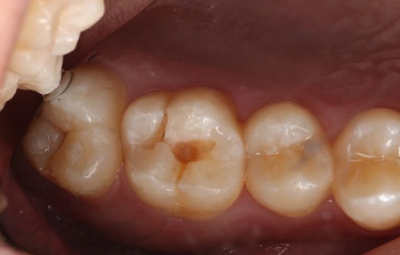

图一:

通关口腔检查以后看到这颗病牙,X片显示龋坏程度尚未及牙髓。判断是龋坏而非牙齿染色,需要进行去龋修补。